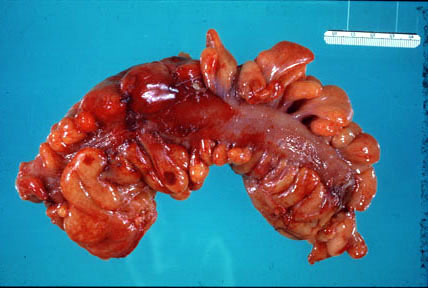

A section of colon reveals numerous diverticula which protrude from the edge of the taenia coli (*). The colon is cut in cross section revealing the diverticuli (contain feces) and the empty colonic lumen. |

A section of colon reveals numerous diverticula which protrude from the edge of the taenia coli (*). The colon is cut in cross section revealing the diverticuli (contain feces) and the empty colonic lumen. |

| Acute Diverticulitis: A section of colon reveals acute inflammation (hyperemia, swelling) of the serosa and pericolic fat. |